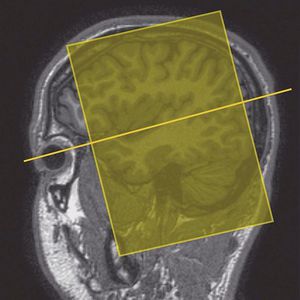

Coronal oblique imaging of the temporal lobes. Slices are angled perpendicular to the temporal lobe (or perpendicular to the axials) (Westbrook C., 2014).